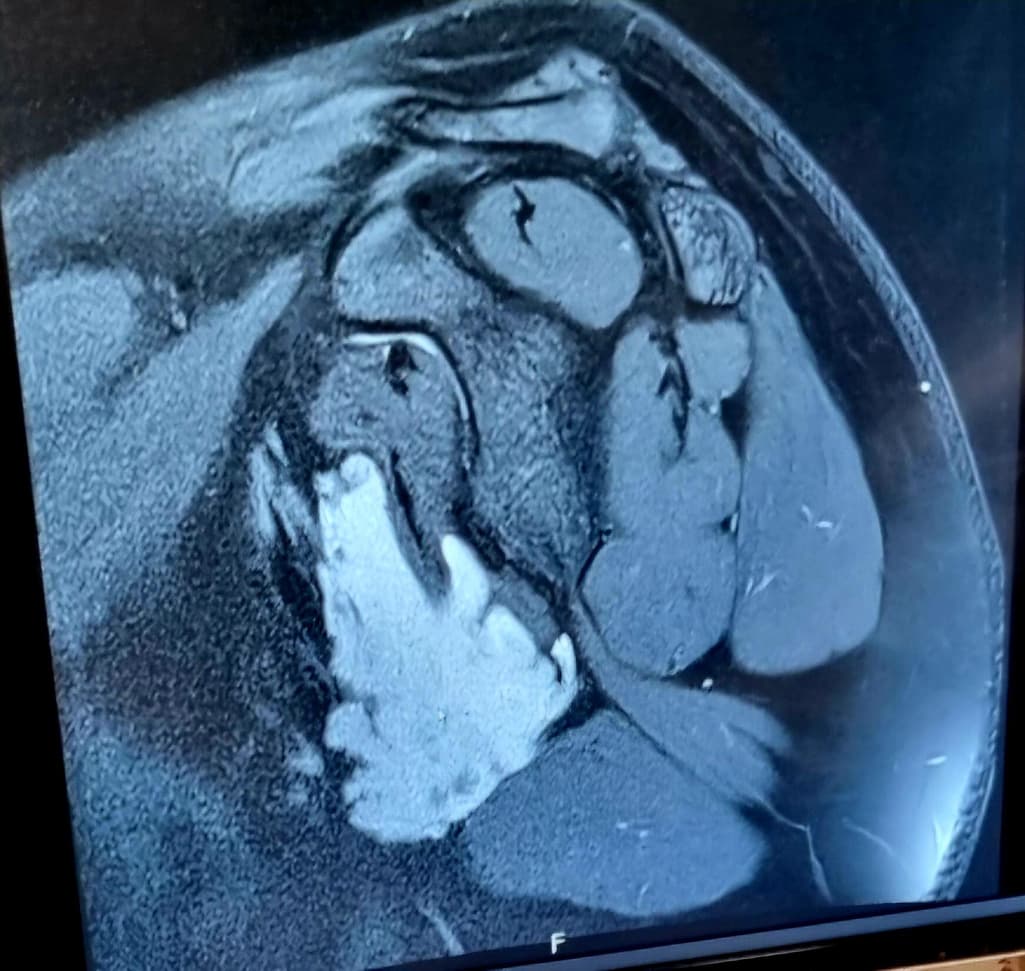

어깨 견관절 결절종인데 액와부에 생겻답니다

MRI 사진좀 확인해주세요 워치가 주사로 뽑을수있는 위치일까요?? 아니면 수술받아야하나요 MRA 촬영이 필요한걸까요??

액와부에 둥글고 밝게 보이는 부분이 결절종으로 추정되지만, 정확한 크기, 주변 조직과의 관계, 내부 상태 등을 파악하기 위해서는 MRI 영상의 다른 단면들을 추가적으로 확인해야 합니다. 결절종의 위치와 액체 점성도에 따라 주사 흡인을 시도해 볼 수 있으나, 액와부의 주요 구조물과의 근접성, 결절종의 크기, 내부 액체의 점성, 다발성 여부 등에 따라 어려울 수 있어요판단 결과 주사 흡인이 어렵거나 재발이 잦고, 주변 조직 압박으로 인한 증상이 있다면 수술적 제거를 고려해야 합니다. 수술은 완전 제거가 가능하지만 흉터와 회복 기간이 필요하구요. 결절종이 혈관 주변에 있거나 수술을 고려한다면 MRA 촬영을 통해 혈관 구조를 자세히 확인하는 것이 도움이 될 수 있습니다.

따라서, 현재 MRI 사진만으로는 정확한 치료 방침을 결정하기 어려우며, 담당 의사와의 직접적인 상담과 진찰을 통해 결절종의 상태를 정확히 진단받고 적절한 치료 계획을 세우는 것이 가장 중요합니다